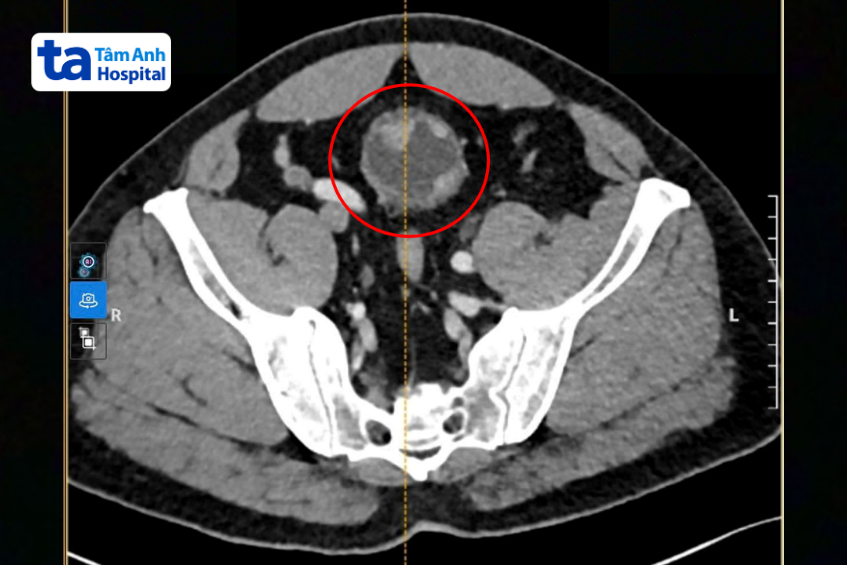

Khi đến khám tại Bệnh viện Đa khoa Tâm Anh TP HCM, bác sĩ siêu âm và nội soi bàng quang phát hiện khối u có đường kính khoảng 4-6 cm. Kết quả sinh thiết xác định u ác tính và đã có dấu hiệu xâm lấn vào lớp cơ bàng quang.